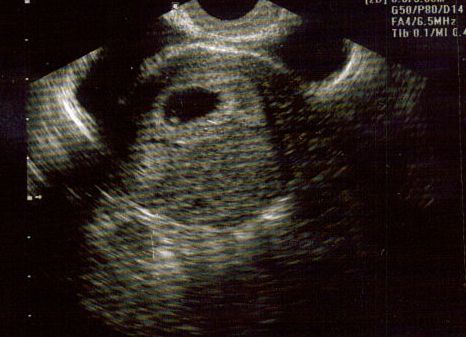

10 week sono today (PICS)

Just wanted to share a pic from my 10 week sono. I cant believe how much has changed since wk 6. At 6 weeks it was literally a dot, I had no idea I would be able to actually see this much today. It was so incredible bc at one pt the baby started "dancing"...DH and I couldnt stop crying...

Top pic is @ 10 wks Bottom pic is @ 6 wks